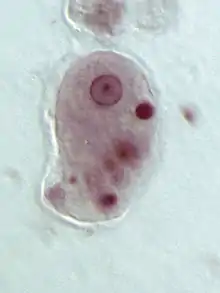

Parasites present one of the biggest threats to health in Guatemala. Many of the common parasites in developing countries like Guatemala are spread through contamination of both water and food.[18]: 32 Some of the effects of parasites include intestinal obstructions, which can hinder the body from absorbing nutrients, lead to a loss of appetite, impair long term growth, induce vomiting, cause anemia and anorexia, and in severe cases, cause death.[18]: 32 Symptoms can also include intense abdominal pain, loss of appetite, nausea, diarrhea, and fever.[18]: 32

It has been seen that the prevalence of parasites is significantly higher among younger children and those who are malnourished.[18]: 35 Parasites are usually transferred through contaminated water, making them dangerous because they are able to induce malnutrition by consuming the body's nutrients, thus impeding a child's physical development.[22]: 97 For school children who are infected with parasites, cognitive functioning can drastically decrease, directly impacting their education.[23] School children who have been treated for parasites immediately perform significantly better in school settings. Parasite infections can also vary based on access to clean water and whether or not sewage disposal is present.[18]: 38 The Millennium Development Goals discussed the importance of deworming to help meet the goals set by the United Nations.[24] Parasites can have serious long-term consequences in that they directly affect development and health for decades after. However, inexpensive, single-dose medications exist that can fully treat these parasitic infections.[24]